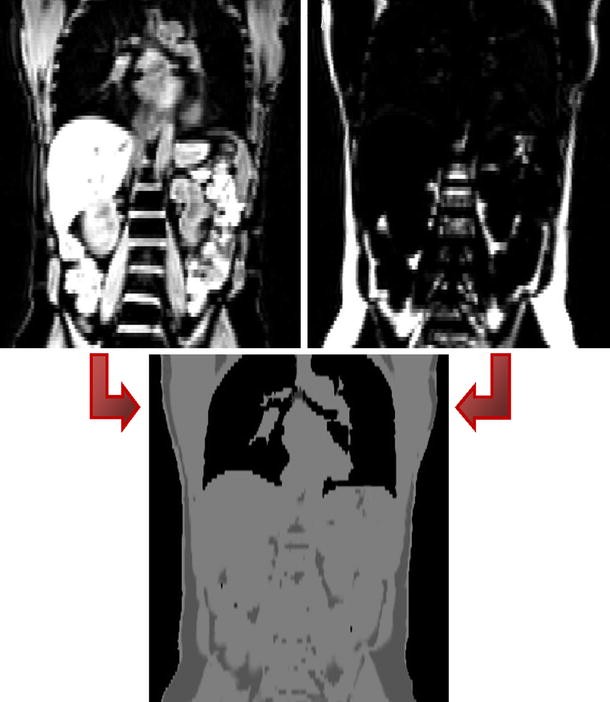

Dixon-based segmentation for whole-body attenuation correction shown in [44] (courtesy of A. Martinez-Moeller): MRI water (top left) and fat (top right) images acquired with a 2-point Dixon sequence are combined and segmented to generate the attenuation map for lungs, adipose tissue, soft tissue, and background